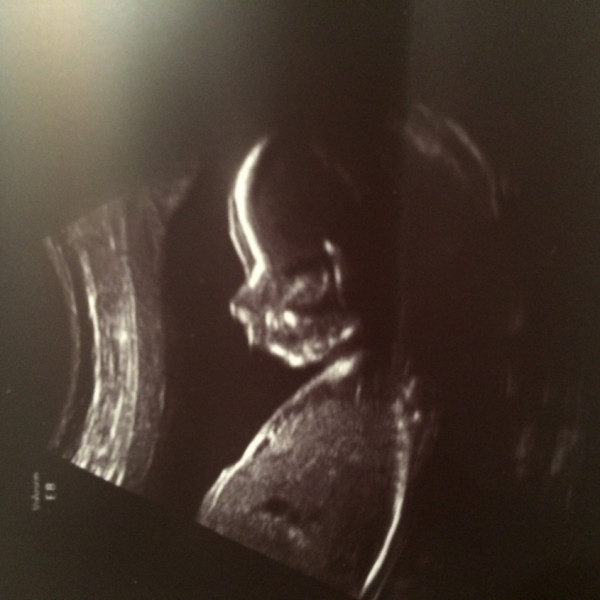

Беременность 22 недели мальчик

Беременность 22 недели мальчик 115 фото